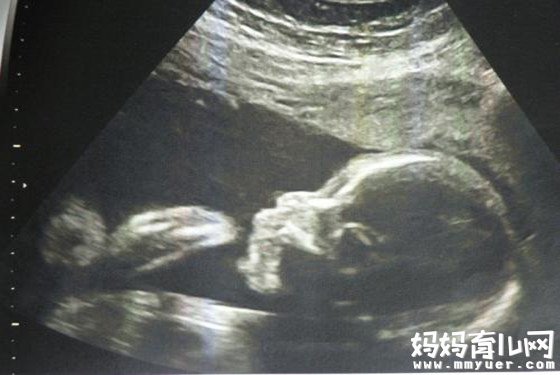

怀孕八个月男胎儿图